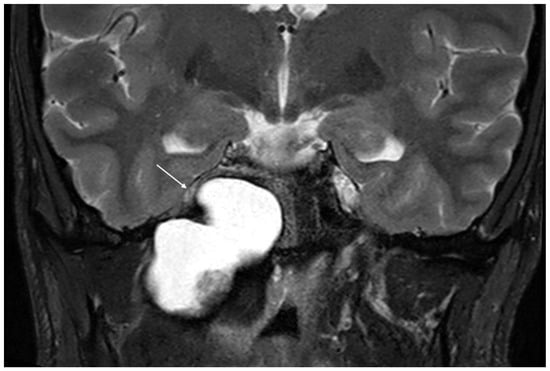

Imaging data from each patient were examined by an expert radiologist and an ENT specialist focusing attention not only on the location of the cyst, but also on the adjacent structures involved. Considering the available literature on symptoms and hypothesized regions of radiological involvement, we established a reproduceable pre-operative radiologic map to better correlate typical symptoms, such as headache, hearing loss, vestibular symptoms, tinnitus, otitis media, diplopia, and facial paresthesia, with PACG. The following regions were considered: (1) temporal lobe/posterior fossa compression (Figure 1); (2) Meckel’s cave compression (Figure 1); (3) Eustachian tube compression/erosion (Figure 2); (4) internal auditory canal erosion (Figure 3); (5) cochlear basal turn erosion (Figure 4); (6) Dorello canal involvement (Figure 5); (7) jugular tubercle erosion. The latter parameter was introduced to evaluate its possible correlation with an atypical clinical presentation, namely fainting. To standardize all these radiological examinations, the jugular tubercle was defined in axial sections as the bony convexity medial to the jugular foramen just above the hypoglossal canal; in coronal sections, it is the bony part directly above the hypoglossal canal (Figure 6).

Figure 5. Axial T2-weighted MRI showing indirect compression of Dorello’s canal (white arrow) by a cholesterol granuloma of the petrous apex.